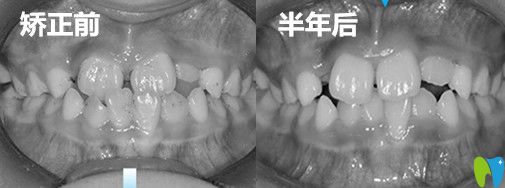

兒子地包天矯正前后效 果對比圖:

成都金琴口腔兒子地包天矯正前后<span style=

從對比圖中,不難看出孩子的牙齒已經有了很大的變化,嘴型也發(fā)生了很大變化,之前閉嘴的時候,下巴稍微有點前突,現在輪廓也得到了不錯的改善!